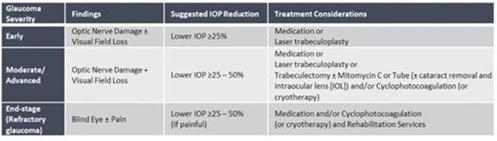

CBN is also the active ingredient in our second drug candidate, INM-088, which is in preclinical studies as a potential treatment for glaucoma. We are conducting studies to test INM-088’s ability to provide neuroprotection and reduce intraocular pressure in the eye. We compared several cannabinoids, including CBD and THC, to determine which cannabinoid was the best drug candidate for the treatment of glaucoma. Of all the cannabinoids examined in preclinical studies, CBN demonstrated the most optimal neuroprotection effect. Furthermore, CBN also exhibited intraocular pressure reduction capability. INM-088 is in advanced formulation development.

Current treatments for glaucoma primarily focus on decreasing fluid build-up in the eye. Our data has shown that INM-088 may provide neuroprotection in addition to modulating intraocular pressure by improving drainage of fluid in the eye. Thus far, we have conducted numerous preclinical pharmacology studies to demonstrate these effects.